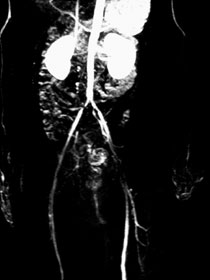

症例9 MRA / CT

ABI:右0.7 左0.9 (高度石灰化)

当日考える

52歳 DM・CRF→HD中

54歳 狭心症→PCI